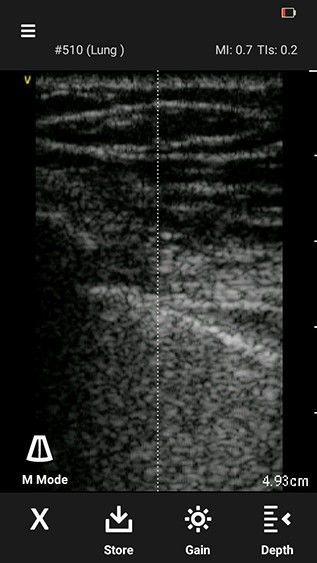

2. Press M mode icon again to enter full M-mode display.

M-mode image

The image freezes automatically once the M-mode display fills. Alternatively an indicator line is seen after 10 seconds of display filling. Also the image can be freezed manually.